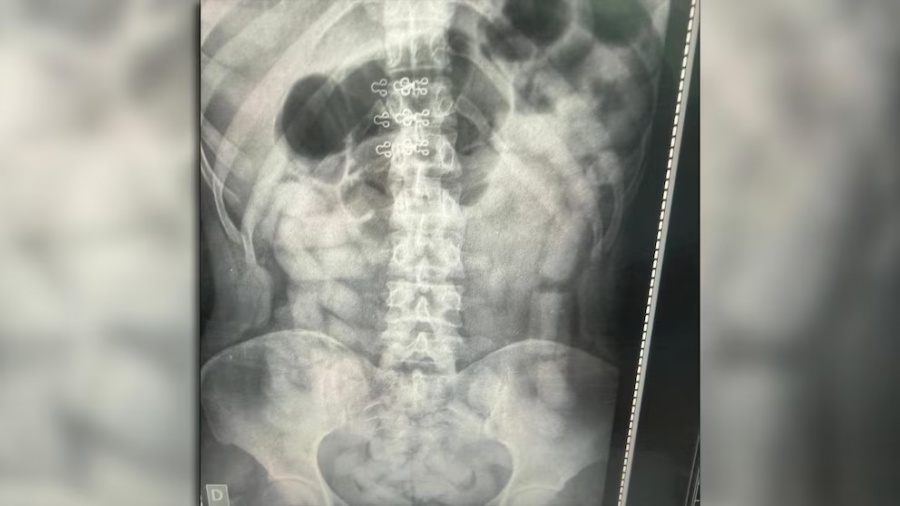

A la mañana siguiente, las sospechas sobre el uso de la modalidad de “mulas” llevaron a que se practicaran placas radiográficas a todos los pasajeros. Las imágenes revelaron cuerpos extraños en el abdomen de cuatro mujeres y dos hombres, una de las placas ilustra este artículo. La modalidad es altamente peligrosa para la salud.

Los seis pasajeros identificados fueron internados bajo custodia en los hospitales de Santa Ana y Los Sarmientos, donde expulsaron un total de 503 cápsulas con un peso superior a los 6 kilos de cocaína. El área de Criminalística y Estudios Forenses contabilizó un total de 752 cápsulas con 10 kilos 316 gramos de la droga.